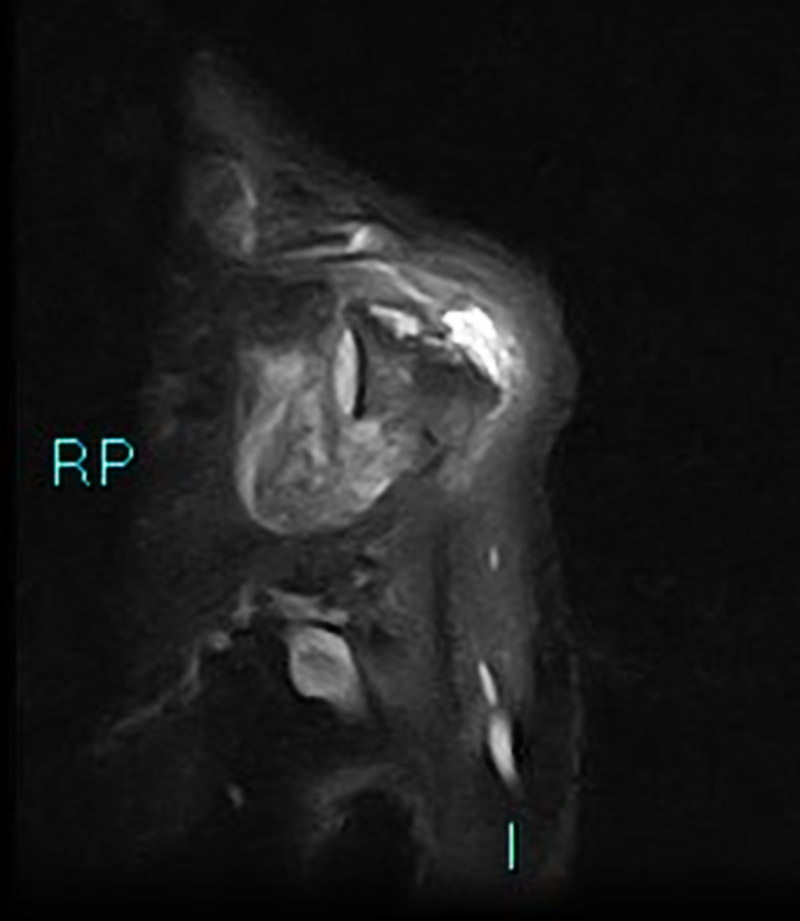

Chụp cộng hưởng từ (MRI) sử dụng từ trường và sóng vô tuyến do máy tính tạo ra để phác họa hình ảnh chi tiết về các cơ quan, mô trong cơ thể. Máy MRI được minh họa như một khối nam châm lớn. Khi người bệnh nằm bên trong, từ trường hoạt động với sóng vô tuyến và các nguyên tử hydro của cơ thể để tạo ra hình ảnh mặt cắt ngang.

Chụp MRI có thể được sử dụng để chẩn đoán các vấn đề về khớp, gồm: